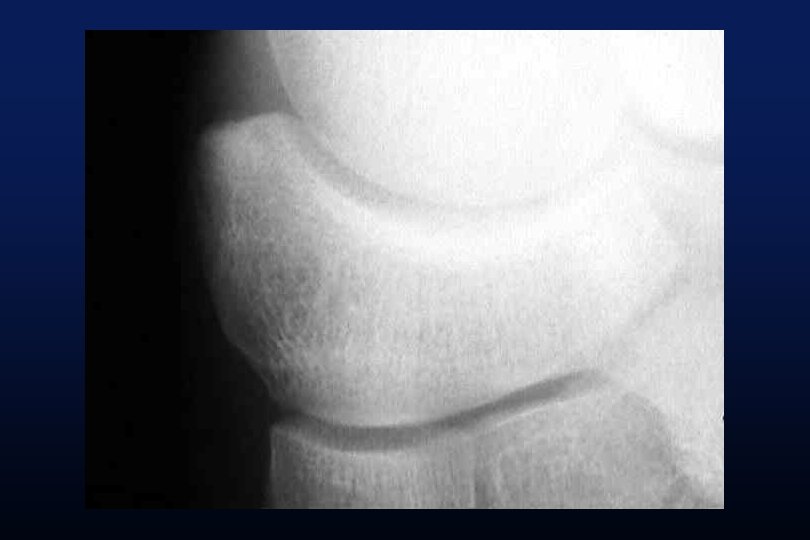

LES SYNOSTOSES DE L ’ARRIERE PIED Coalitions Tarsiennes (Tarsal Coalitions)

CALCANEO NAVICULAIRES (60%) TALO CALCANEENNES Synostoses et coalitions tarsiennes chez l'enfant. Étude de 68 cas chez 47 patients Ph. Rouvreau, J. C. Pouliquen, J. Langlais, C. Glorion, G. de Cerqueira Daltro The Too-Long Anterior Process Calcaneus: A Report of 39 Cases in 25 Children and Adolescents Pouliquen, J. C. M. D. ; Duranthon, L. D. M. D. ; Glorion, Ch. M. D. ; Kassis, B. Journal of Pediatric Orthopaedics Volume 18(3) June 1998 333 -336